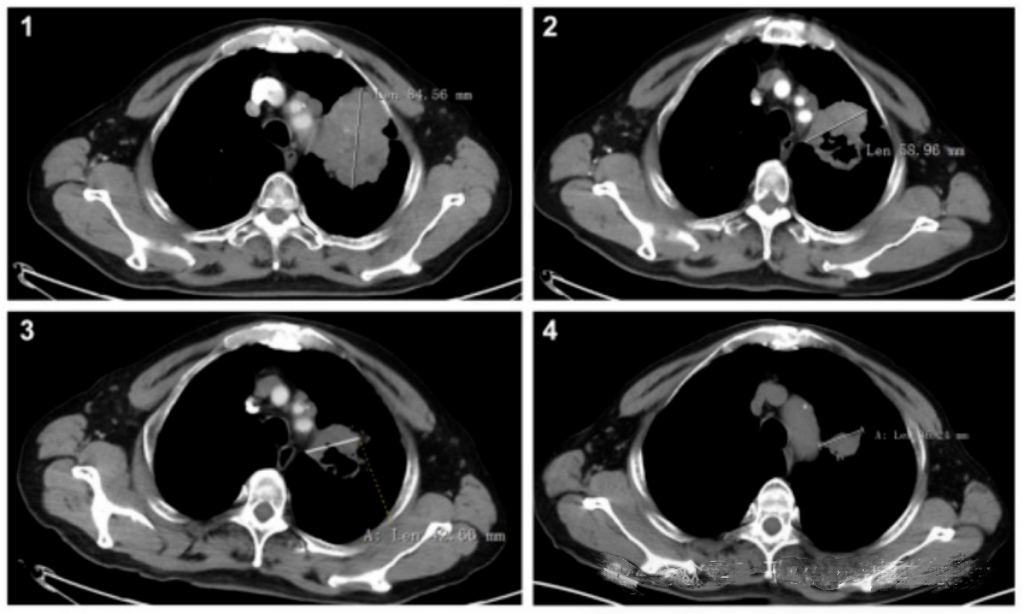

信迪利單抗聯合安羅替尼作為晚期 NSCLC 患者一線治療的 1b 期研究,患者的病灶變化顯示明顯減少

該組和化療組的中位緩解持續時間(DOR)分別為16.3個月和6.2個月,中位無進展生存期(PFS)分別為10.8個月和5.7個月,風險比(HR)為0.4,表明疾病進展的風險減少了60%,P=0.002。